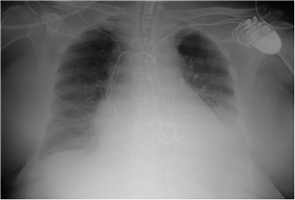

El día de la intervención se realizó esternotomía de forma rutinaria por un cirujano experto mediante el empleo de una sierra recta tras lo que se produjo un sangrado masivo venoso súbito. Se observó junto con la hemorragia la aparición de electrodos en cavidad mediastínica. Una vez controlado el sangrado, la rotura del tronco venoso braquiocefálico y ambos electrodos de estimulación cardiaca con la sierra de apertura esternal, se hizo evidente. Se realizó ligadura de ambos extremos de la vena innominada para conseguir un definitivo control del sangrado incluyendo los extremos de ambos electrodos seccionados (Ver Figura 3). Se comprobó que el corazón latía espontáneamente sin cambios electrocardiográficos y la paciente presentó normalidad hemodinámica. Tras la sutura del tronco braquiocefálico se procedió a realizar la intervención sobre la válvula mitral de manera rutinaria, sin incidencias y con normalidad en cuanto al ritmo cardíaco.

Figura 3 Radiografía antero-posterior de tórax postquirúrgica con rotura de los electrodos..

En este caso el tratamiento conservador mediante la ligadura de ambos extremos de la vena innominada resultó satisfactoria con implante de marcapasos al final de la intervención mediante la colocación de cables de estimulación epicárdicos. Debido a la ausencia de arritmias cardiacas en el momento de la intervención no se experimentó eventos adversos